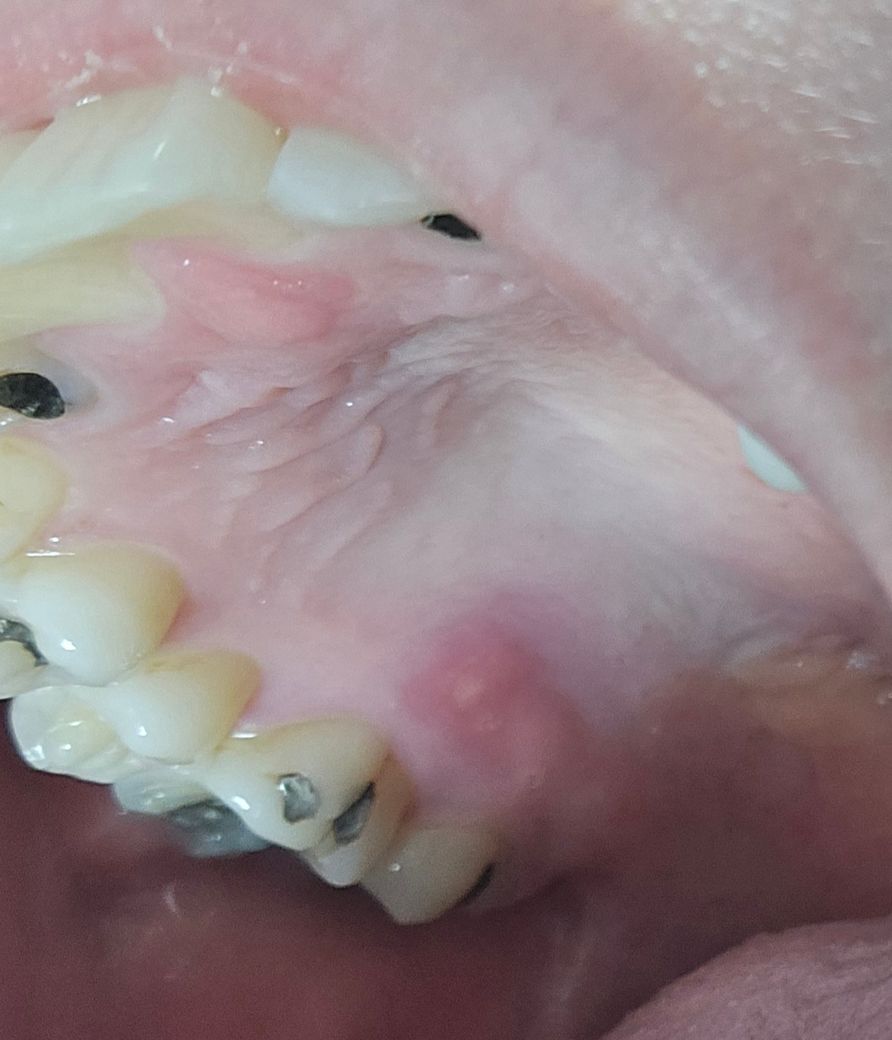

오른쪽 입천장에 물집이 났는데 치근단 농양일까요?

어제부터 느꼈던 물집인데 뭔가 볼록 튀어나와있습니다.

씹을 때 통증 없고, 뜨거운 거 차가운 거 통증도 없어요. 혀로 건들때도 통증없고, 가만히 있거나 야밤에도 통증이 없는데 튀어나온 부분을 손으로 누르면 아프네요.

• 1번 째 사진